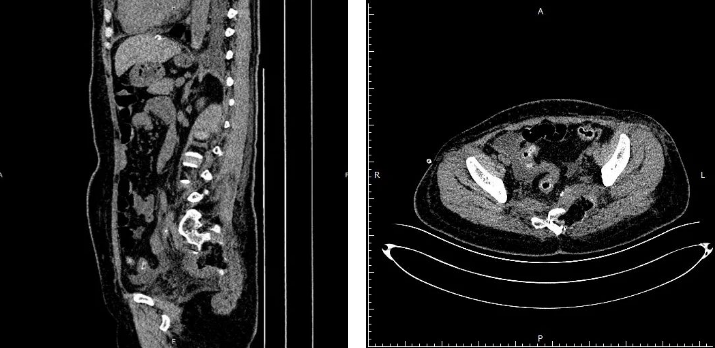

患者韩某,女,49岁,一个多月前,不明原因出现腰骶部疼痛,难以忍受,骶尾部及左侧臀部压痛,左侧臀部及会阴部感觉减弱,口服镇痛药洛索洛芬钠片对症治疗,不见好转,随后就诊于我院,医生查骨盆MRI示:骶椎左侧占位性病变。

经神经外科程主任细致查体,结合患者症状与影像学表现,与王教授制定了详细的手术方案,拟于显微镜下行骶椎左侧占位切除术,术中彻底清除肿瘤以及被侵蚀的骨性组织。术后患者症状明显好转。